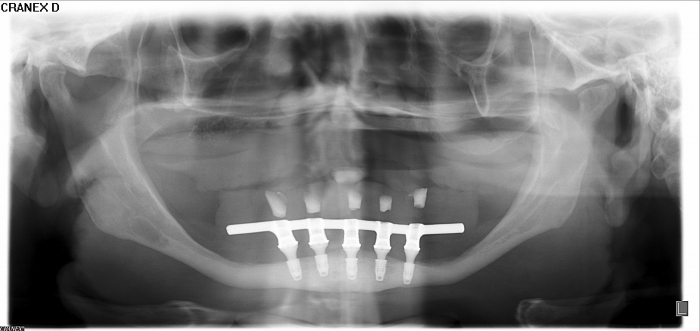

Raio-x Implantes com Prótese Fixa Definitiva em Resina

Prótese fixa sobre os implantes inferiores e nova prótese total superior, em Janeiro de 2016

Sorriso Final, em 2016